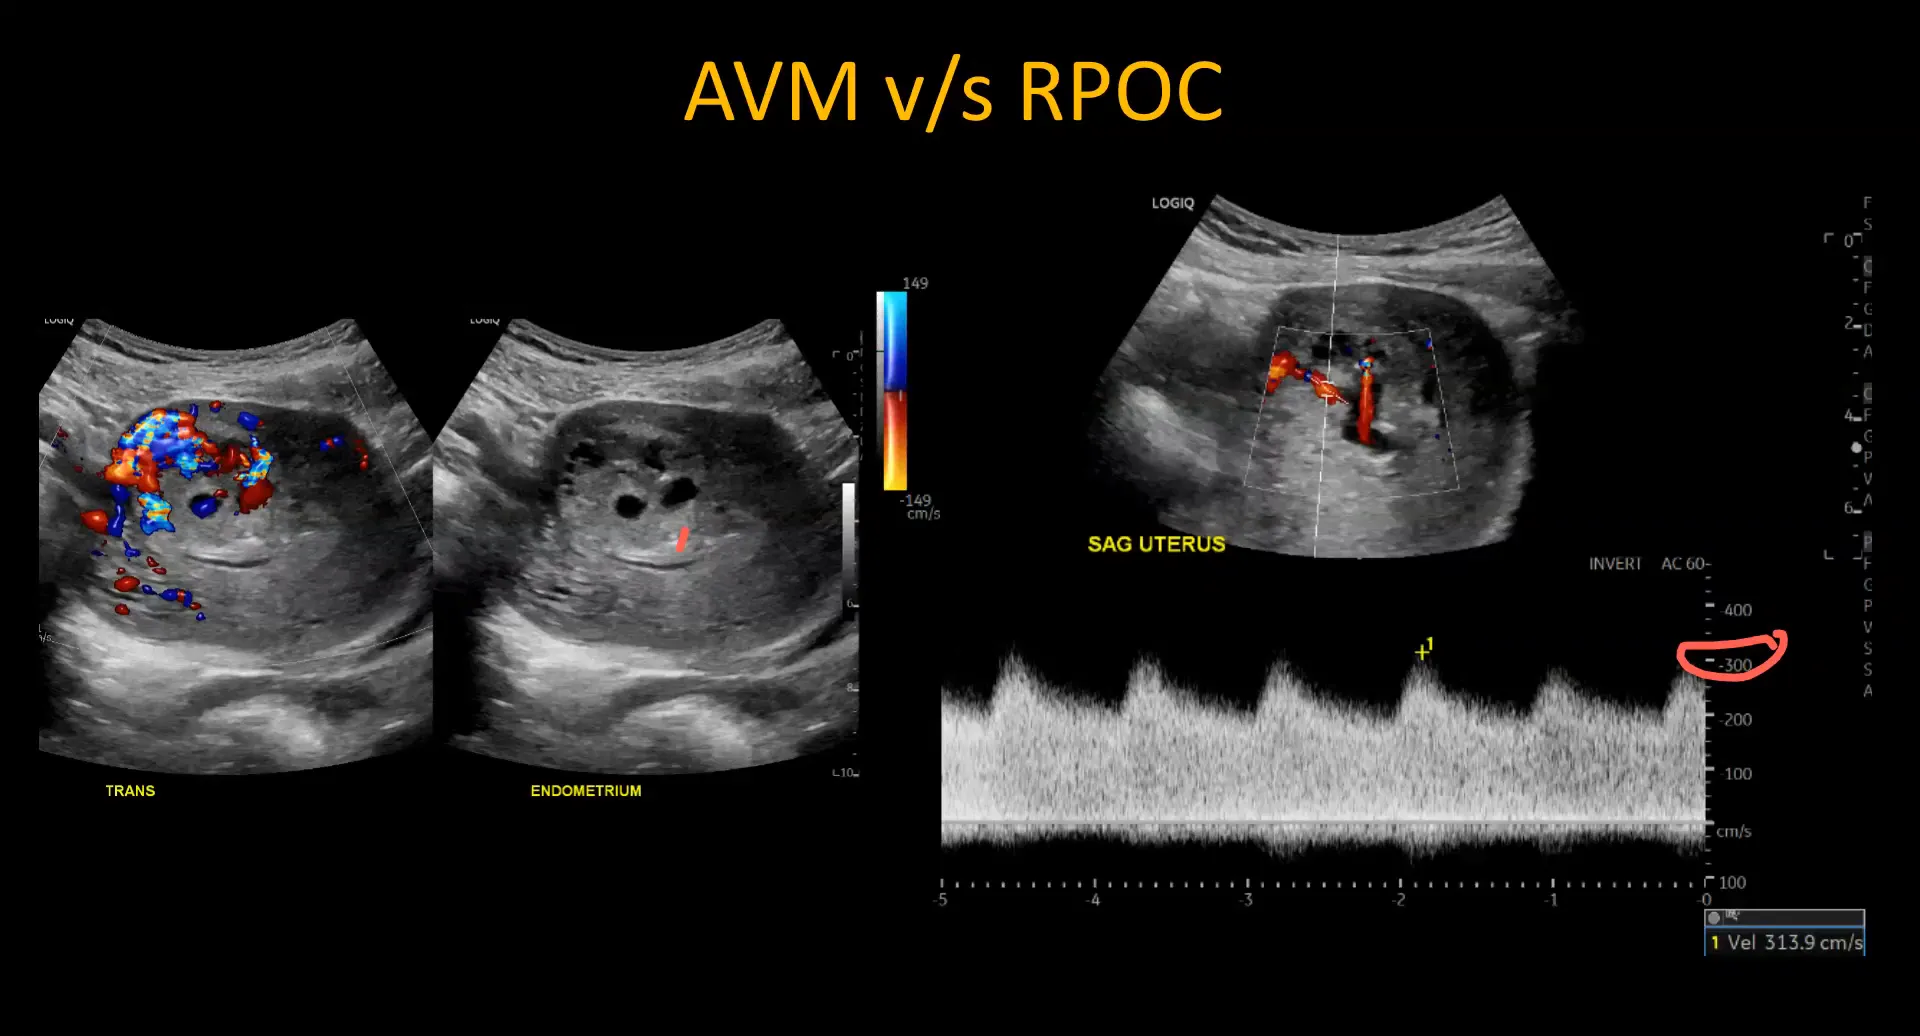

Differentiating RPOC from AVM

Differentiating Retained Products of Conception (RPOC) from Arteriovenous Malformations (AVMs) is crucial due to their differing management strategies. While both may present with similar ultrasound findings, key differences exist.

- Vascularity Location: In RPOC, vascularity is centered on the endometrium, whereas in AVMs, it is located within the myometrium.

- Flow Characteristics: AVMs typically exhibit very high peak systolic velocities (>200-300 cm/s) with significant diastolic flow, which is not usually seen in RPOC.

Recognizing these differences can prevent complications during surgical interventions. Doppler ultrasound is essential for accurate diagnosis.